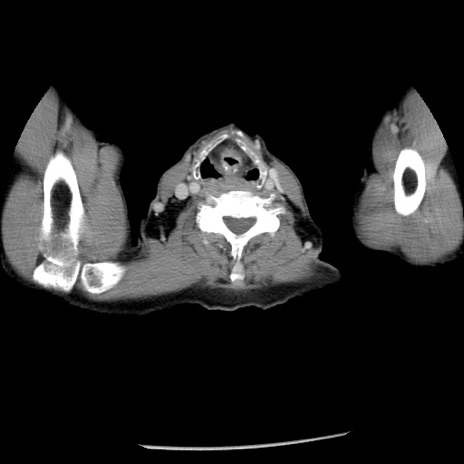

症例26(横断像)

【症例】80歳代男性

【主訴】嘔吐

【現病歴】昨晩2回嘔吐あり、今朝になっても嘔吐あり。来院。

【既往歴】胃潰瘍

【身体所見】意識清明、BT 37.6℃、BP 166/95mmHg、HR 100bpm、SpO2 97%、腹部:平坦・軟、腸蠕動音聴取良好、圧痛なし。

【データ】WBC 21900、CRP 1.46